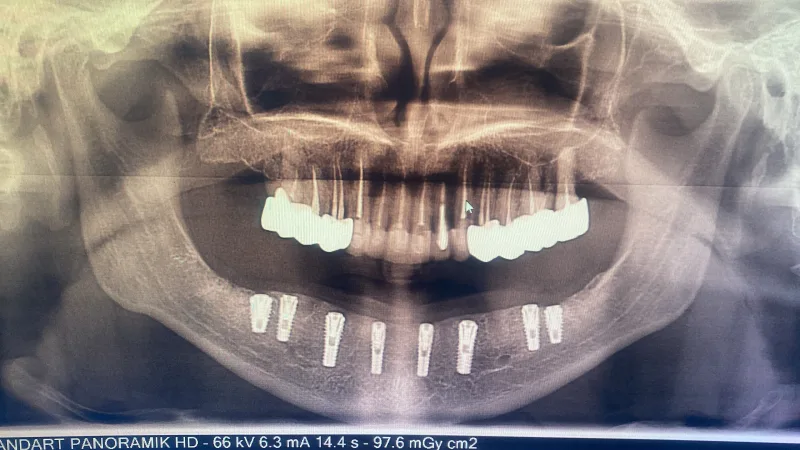

✅ Протезирование и имплантация зубов